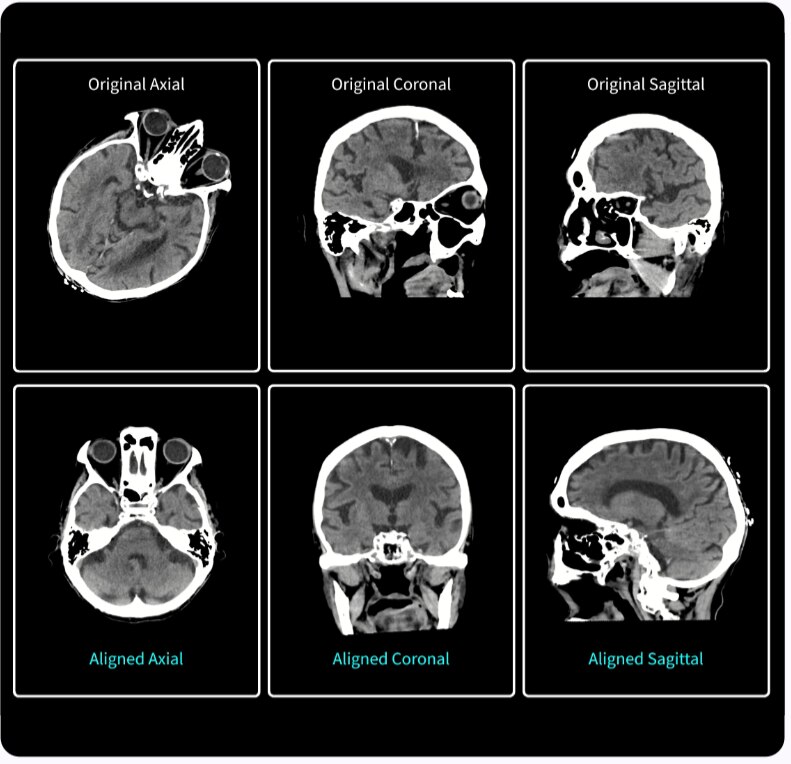

Nuestra cámara Xtream utiliza tecnología de detección precisa en tiempo real para generar un modelo 3D del cuerpo del paciente. A continuación, mediante nuestro algoritmo de aprendizaje profundo, Revolution Advance localiza el centro del rango de exploración y lo alinea automáticamente con el isocentro del túnel. Con un solo clic, el posicionamiento automático utiliza toda esta información para centrar automáticamente al paciente sin necesidad de intervención.

Esta tecnología inteligente proporciona tiempos de exploración más cortos, lo que hace que la experiencia de exploración sea más cómoda para sus pacientes. También ayuda a optimizar la dosis, mejora la calidad de la imagen y proporciona una mayor uniformidad en la exploración.